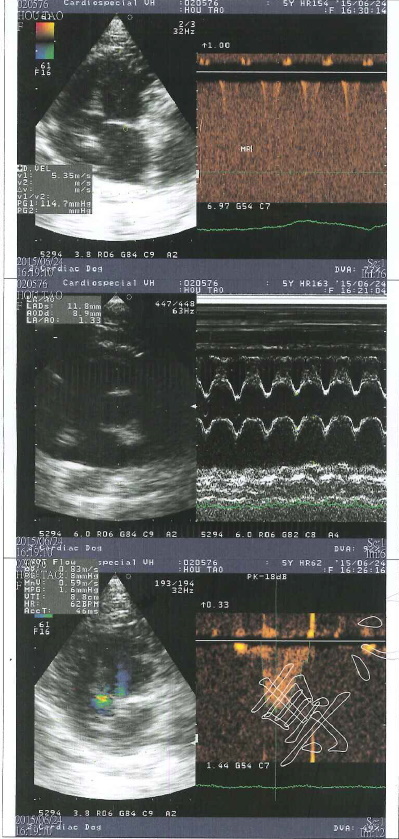

2015/4月厚道食慾胃口下降,就醫檢查發現肝指數較高,超音波無明顯異狀,X光片肺部較多白影處,可能上呼吸道感染,或者是剛救援時感染肺炎的後遺症,給予口服抗生素,因為厚道的牙齒所剩無幾,又口炎需要噴口樂減緩不舒服,因為肝指數偏高每天需要打皮下點滴75CC補充水分,治療後食慾慢慢恢復,五月追蹤肺部狀況進行X檢查,發現心臟旁稍有異樣,建議要轉院進行心臟超音波檢查,約診心臟專科專心動物醫院進行詳細檢查,檢查結果稍微心室肥厚,可能先天就這樣,也不一定會惡化,需半年回診監控情況,最久一年一定要回診掃心超,目前不需吃藥,持續每天打75ml,專心掃描心臟超音波的費用還請各位幫忙。